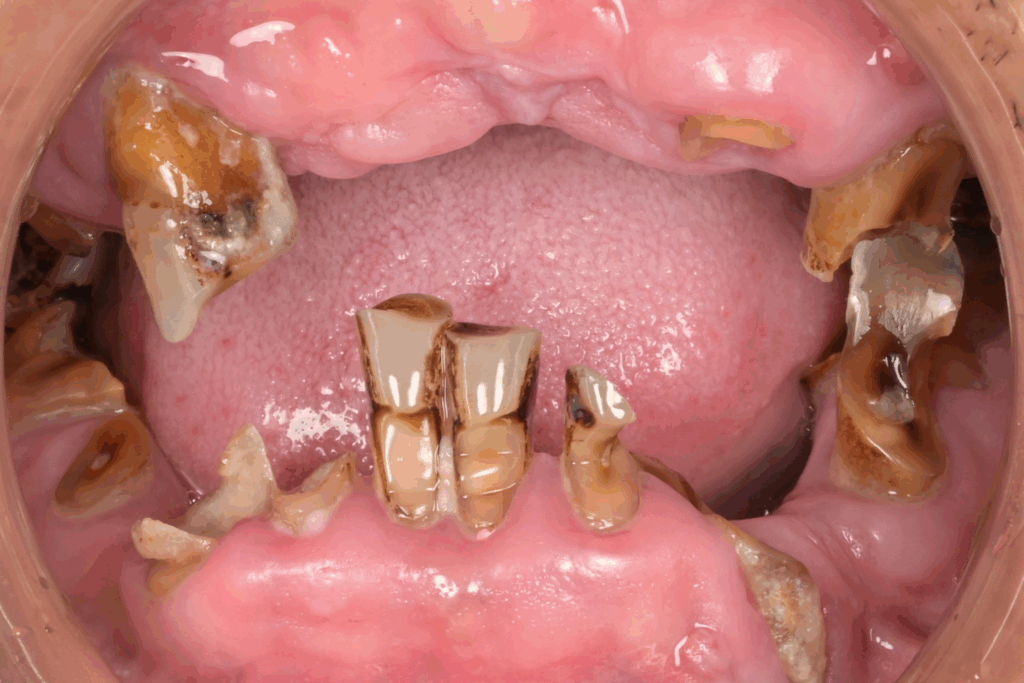

案例1. 上顎+下顎All on X

Before

After